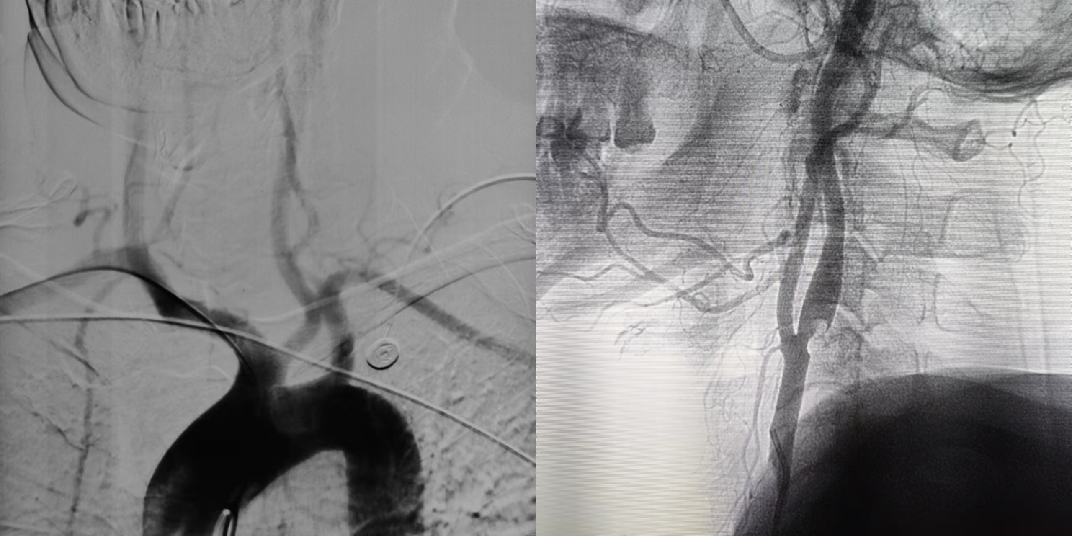

DSA示:牛角弓,左侧颈内动脉起始部狭窄

• 患者左侧颈动脉狭窄,狭窄程度>50%,合并既往左侧颞叶梗塞,具备明确手术指征;患者拒绝行颈动脉CEA手术,要求选择CAS术;患者主动脉弓形为牛角弓,经股建立通路较繁琐,适于经桡建立左侧颈动脉通路;

置入泥鳅导丝后退出短鞘,交换6F Epath长鞘在路图下上行至右侧锁骨下动脉。

利用导丝直接超选左侧颈总动脉开口并将导丝头端置于左侧颈外动脉,引导Epath上行至左侧颈总动脉主干。